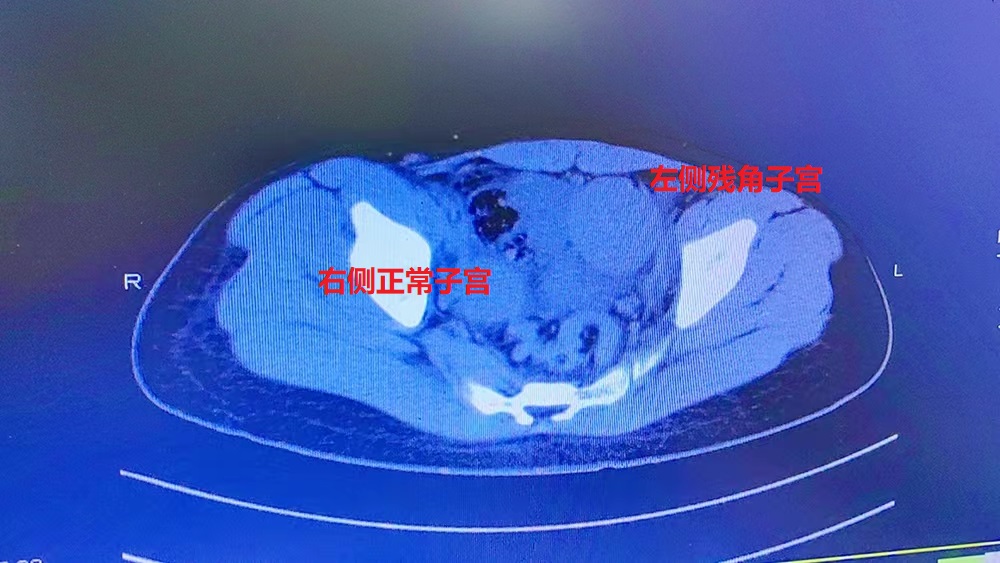

小红入院后,妇科团队立即给予抗感染等对症支持治疗,因其盆腔包块性质难以确诊,且为青春期少女,一旦误诊,切除了不该切除的器官,将对其今后的生活导致及其严重的打击,需详细制定诊疗方案。省人医帮扶专家、县人医副院长陈建国高度重视,立即与放射科组织开展病例讨论,根据三维CT血管成像,最终诊断残角子宫可能性大,小红有剧烈腹痛症状且有丰富血流,考虑为II型残角子宫,需行微创手术切除。

残角子宫为先天发育畸形,是一侧副中肾管发育不全所致,形成单角子宫。II型残角子宫有宫腔及内膜,与正常子宫不相通也可产生经血,但无法排出,从而导致周期性腹痛及残角子宫的宫腔内积血,经血逆流常导致子宫内膜异位症及卵巢巧克力囊肿。常合并有同侧肾脏输尿管发育异常等症状。

在征得小红及其家属同意后,5月25日,妇科团队为其在全麻下行腹腔镜联合宫腔镜探查,术中发现腹腔积血约100ml,盆腔内两个不相连的子宫,行腹腔镜下透光试验,确认左侧子宫为残角子宫,确认后再行腹腔镜下左侧残角子宫切除+左侧输卵管切除+左侧卵巢囊肿剔除术,手术非常顺利,术后在妇科团队的精心照料下,于5月31日痊愈出院。